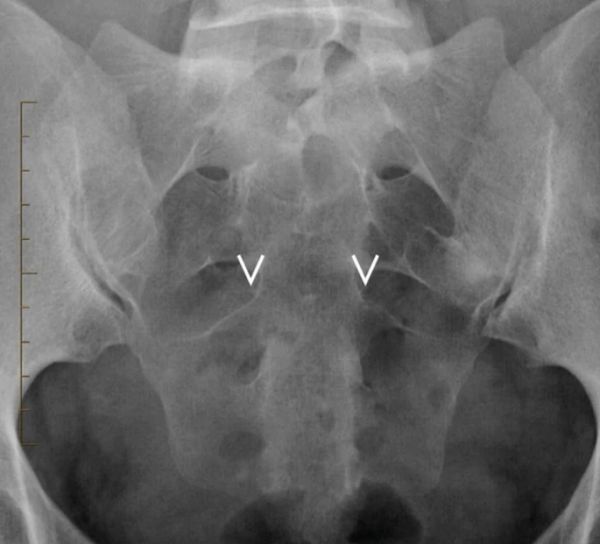

4.如果 S3 孔在透视前/后视图中清晰可见,则标记孔的上部内侧(图10.2)。

5.如果由于覆盖肠内容物而无法识别 S3 孔,则从两条线交叉点上方约 2 厘米和 3 厘米(取决于体型)开始(参见步骤 #3)。将其标记在右侧和左侧(图10.2)。

图 10.2

识别 S3 孔的内侧。